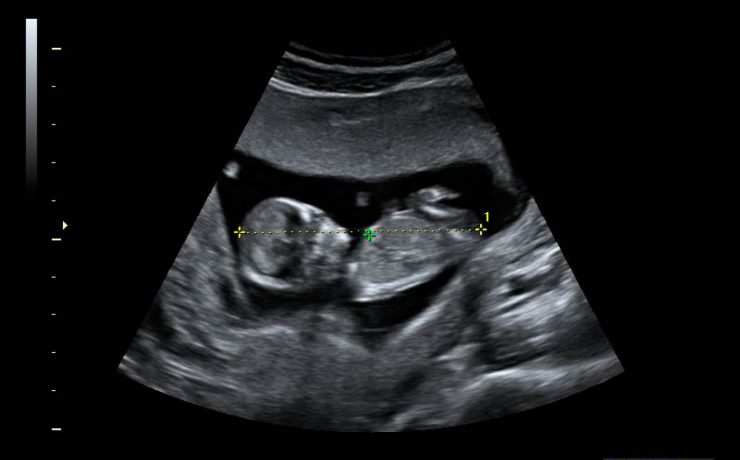

Ultrasonido en el primer trimestre del embarazo, 10 consideraciones básicas.

El ultrasonido es un evento físico natural que siempre ha estado presente en el entorno del hombre; solo fue necesario que personas observadoras, con mentes brillantes, encauzaran su utilización. En el campo médico, el fenómeno del eco ha aportado uno de los métodos diagnósticos más